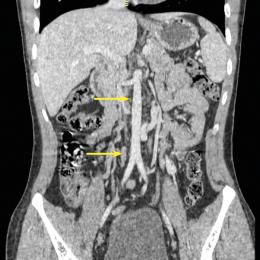

Cystite emphysémateuse

Une patiente de 89 ans, sans antécédent majeur, consulte aux urgences à la suite d’une chute accidentelle avec fracture...